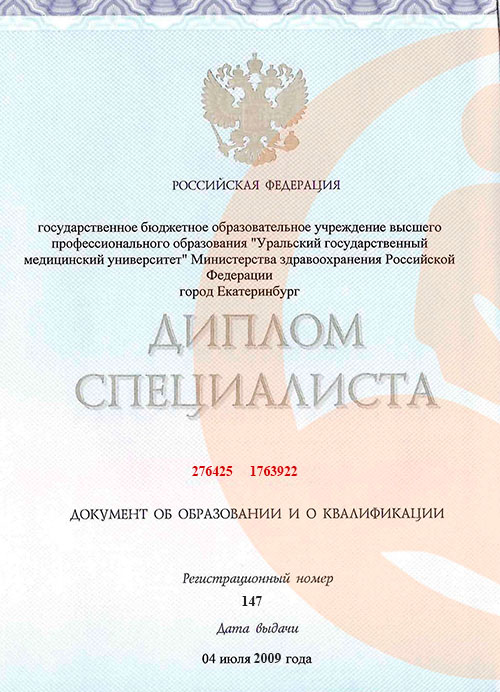

Образование:

- 2009 - Уральский государственный медицинский университет (лечебное дело);

- 2011 - Уральский государственный медицинский университет (Ординатура - анестезиология и реаниматология);

- 2015 - Уральский государственный медицинский университет (Повышение квалификации - анестезиология и реаниматология);

- 2020 - Уральский государственный медицинский университет (Повышение квалификации - анестезиология и реаниматология)

Образование и профессиональное развитие

Андрей Максимович окончил Уральский государственный медицинский университет в 2009 году по специальности «лечебное дело». Уже через два года он успешно завершил ординатуру по анестезиологии и реаниматологии в том же университете, что дало ему необходимую специализацию для работы в области интенсивной терапии и обезболивания. В 2015 и 2020 годах прошёл курсы повышения квалификации по анестезиологии и реаниматологии, что подтверждает его стремление оставаться в курсе новейших методик и практик в своей области.